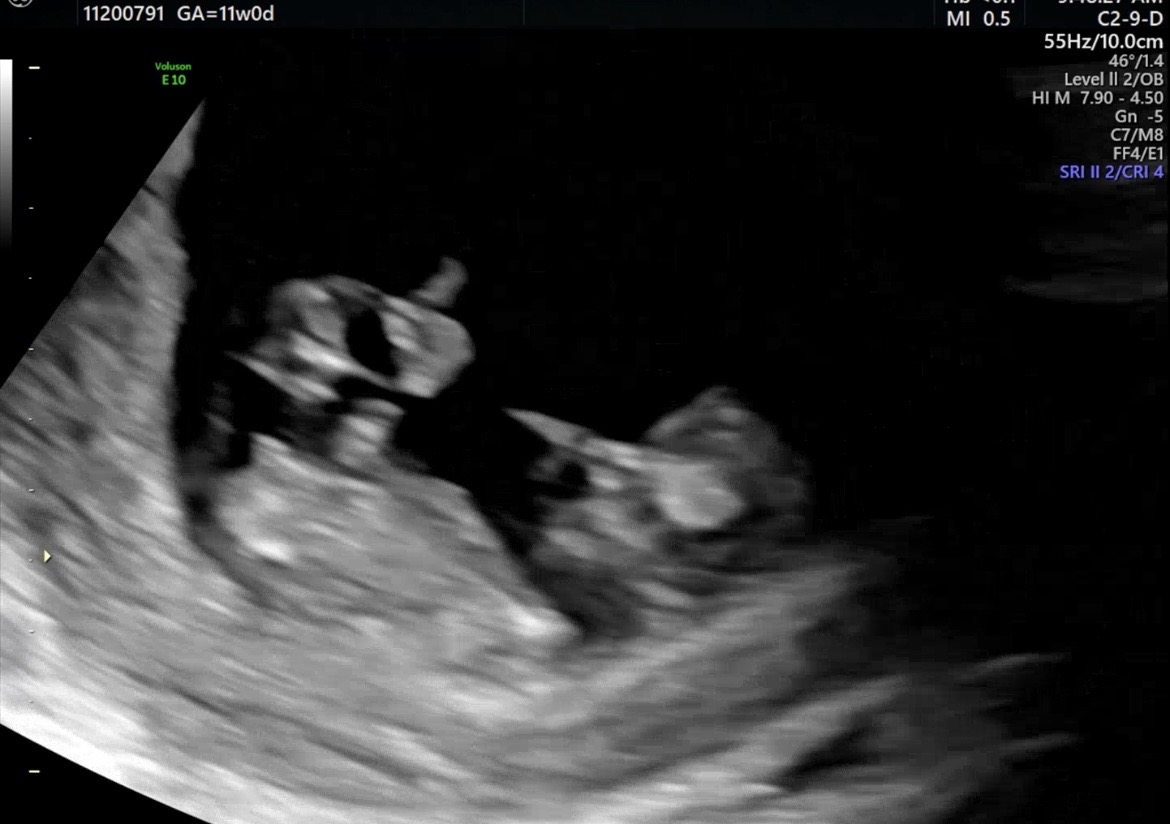

11주 성별 추측 부탁드려요!

11주0일이라 이르지만 성별이 궁금하네요! 혹시 이 사진으로 알 수 있을까요?